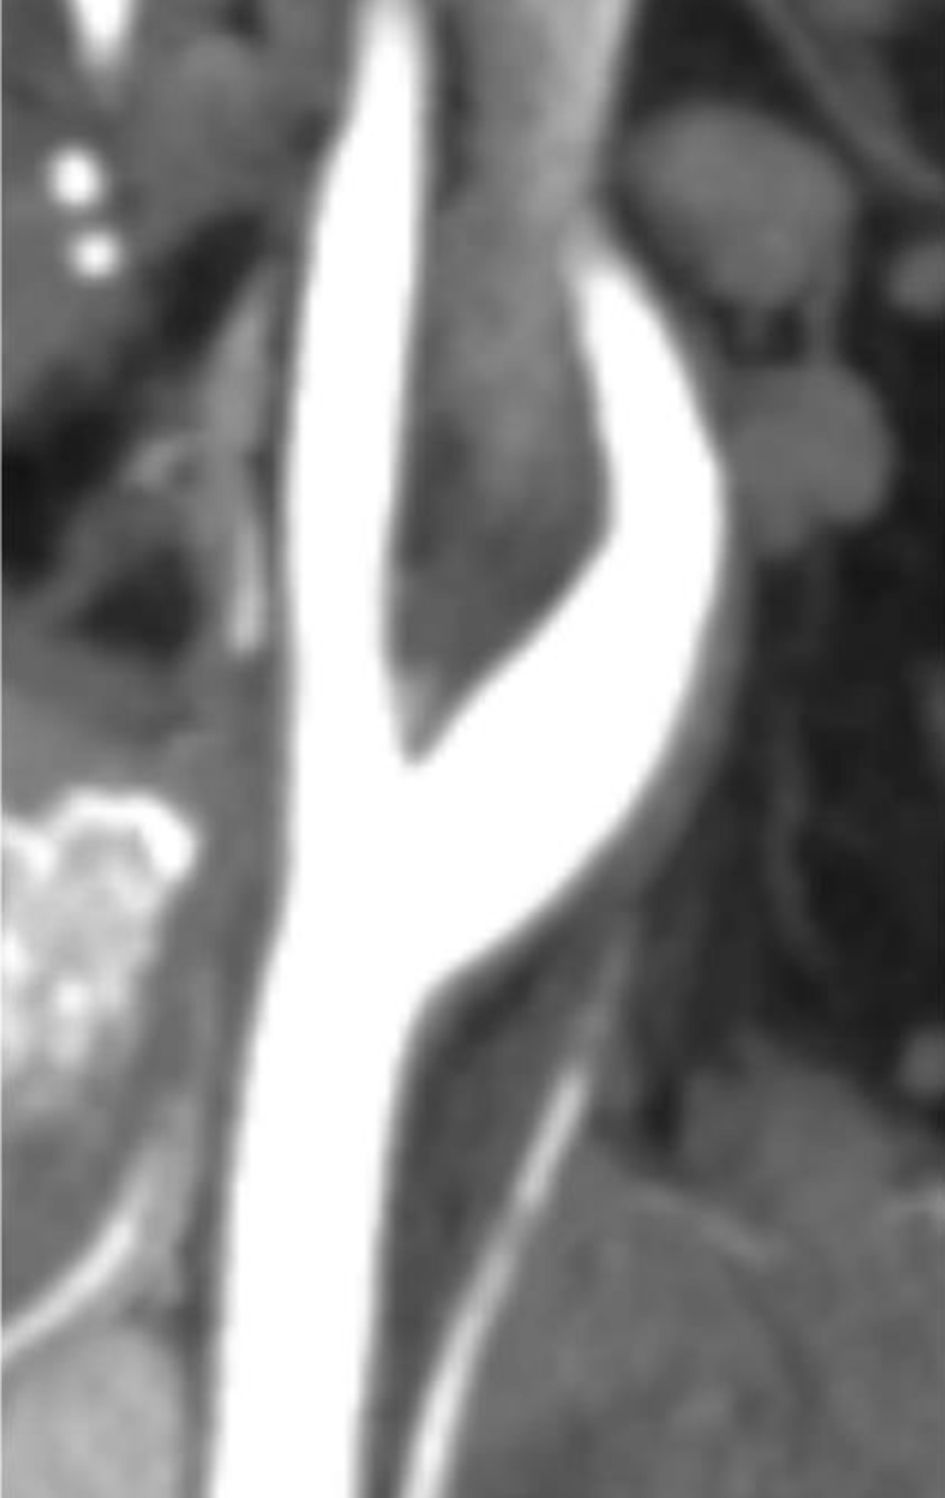

The following day, no apparent hemorrhagic extension was observed. On carotid artery ultrasonography, there was a mobile lesion at the origin of the left ICA (Fig. 2). Further examination with three-dimensional computed tomography angiography (3D-CTA) revealed the presence of irregular contrast in the posterolateral wall of the left cervical ICA origin (Fig. 3a-d). MRI plaque image revealed a structure that was T1 isointense (Fig. 4a) and T2 high intense (Fig. 4b) with the vessel wall, protruding into the lumen (Fig. 4). On the second day, cerebral angiography revealed a shelf-like structure on the posterior wall of the left ICA origin (Fig. 5a), and the left MCA was recanalized. Cerebral angiography revealed pooling of blood flow on the rostral side of the lesion (Fig. 5b).

Figure 3. Three-dimensional computed tomography angiography revealed the presence of irregular contrast in the posterolateral wall of the left cervical internal carotid artery origin. (a) Sagittal image (white arrow); (b-d) axial images (black arrow).

Treatment

Figure 6. Three-dimensional computed tomography angiography performed 86 days after symptom onset showed that the shelf-like structure on the posterior wall of the origin of the left internal carotid artery had disappeared.